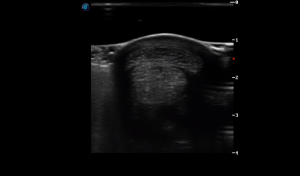

SIMON Ultrasound Database

This ultrasound database is a free resource for students and doctors!

Our collection includes videos of dogs, cats, horses, cows, humans, and many other species!